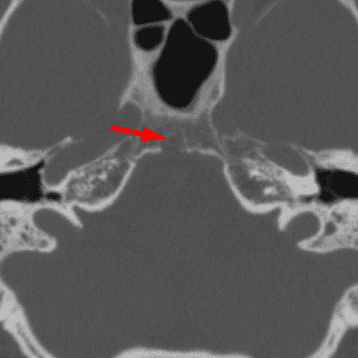

Trochlear Calcification

Case 5